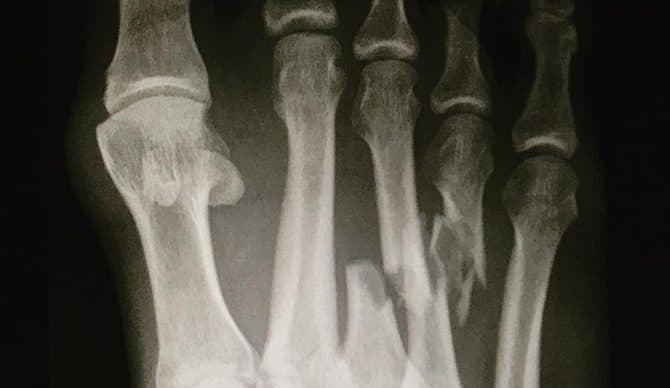

Hỏi bệnh sử và khám thực thể. Chụp X-quang, chụp cắt lớp vi tính CT Scan, chụp cộng hưởng từ.

Click vào ảnh để xem 4 hình ảnh minh họa

Phương pháp điều trị cho chân bị gãy sẽ khác nhau, tuỳ thuộc vào tình trạng xương đã bị gãy và mức độ nghiêm trọng của chấn thương. Nếu gãy xương đơn giản điều trị chỉ cần nẹp cố định và sử dụng nạng khi đi lại để không làm ảnh hưởng đến xương. Gãy xương nghiêm trọng hơn hoặc những người bị dị tật của xương hoặc khớp có thể cần phẫu thuật.